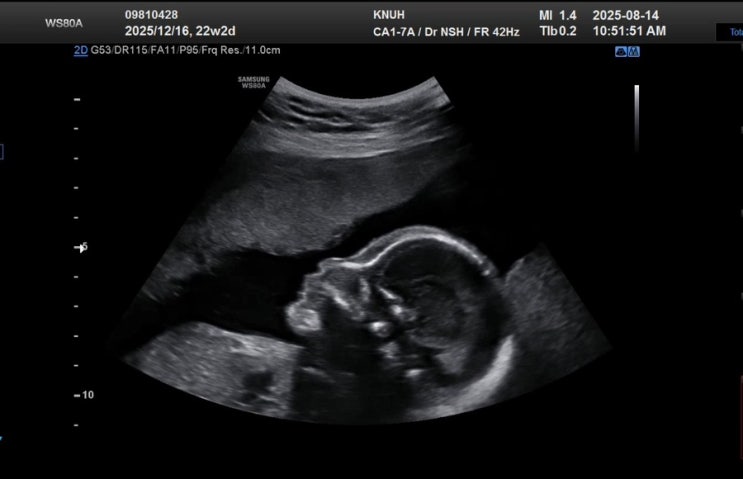

둘째 임신 22~26주 정밀초음파 임당검사

지금은 27주이지만 또 몇주간 엄청난 일들이 있었지만 그만 미루고 포스팅을 마무리해본다 임신 22주에 보...